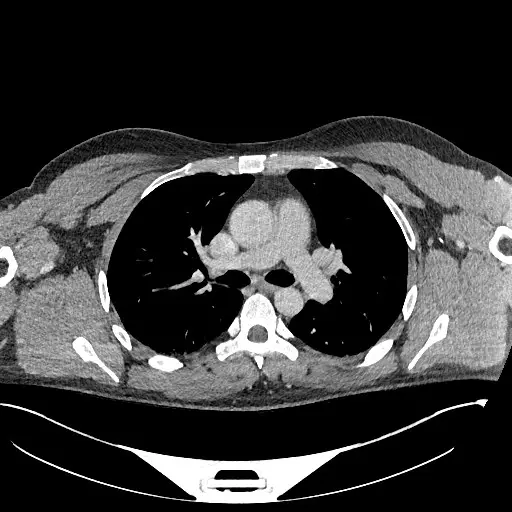

Figure 1: CT chest without contrast